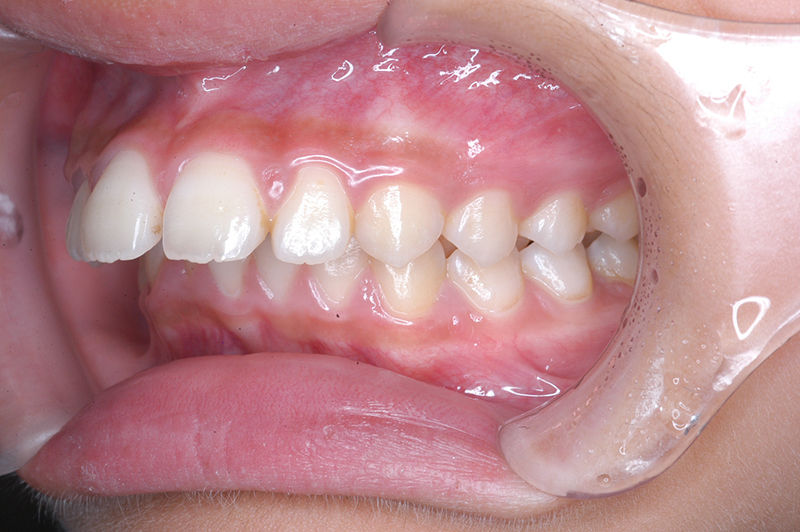

初診時

FP・IOP

口腔内所見 大臼歯関係は右側がエンドオンのclassⅡ、左側がfull classⅡ。 上顎正中は下顎正中に対して僅かに右側偏位しており、上顎前歯は大きく唇側傾斜しover jetが11.0mmと上突咬合を呈していた。また下顎歯列の緩やかなスピーカーブのため過蓋咬合(over biteは5.0mm)となっていた。